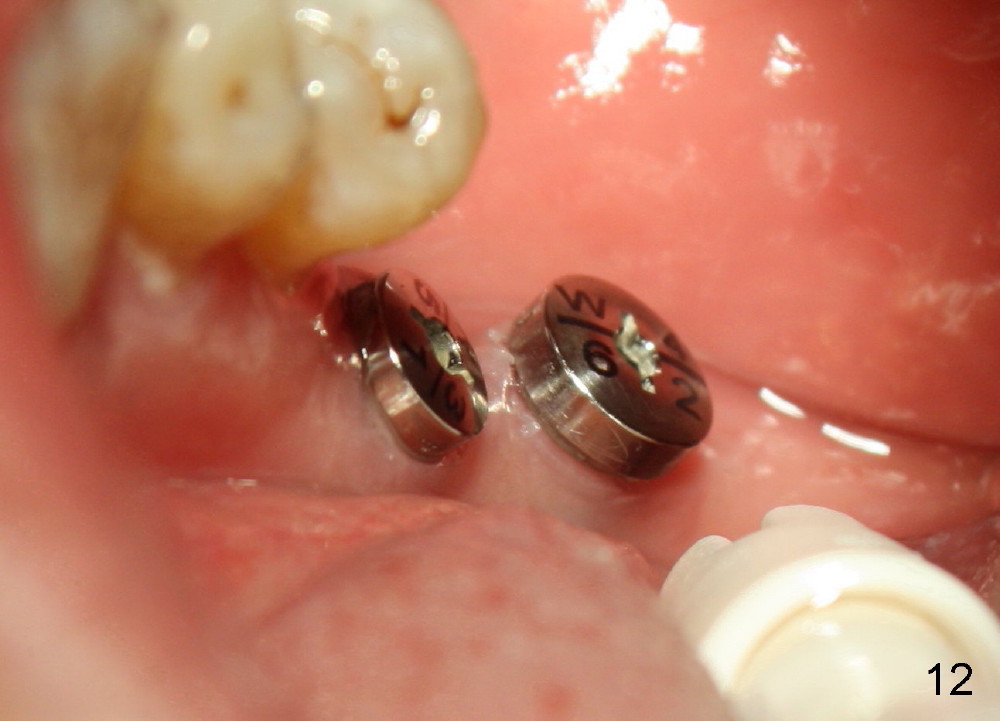

![]() |

One week postop, the gingiva buccal to #30 healing abutment was reddish (at the area indicated by arrowheads in Fig.10,11). The patient complained facial swelling. Clindamycin was taken one extra week to help resolve postop infection. By 24 days postop, there is no infection around these two healing abutments (Fig.10-12). The patient is pleased and makes an appointment for #18 implant placement (Fig.1), which is more challenging.